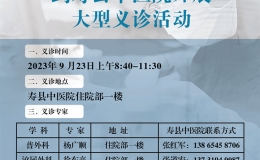

【医讯】上海知名专家到寿县中医院开展大型义诊活动

来自上海交大附属瑞金医院、上海复旦附属肿瘤医院、上海交大附属皮肤病医院、上海同济附属医院、上海东方医院等8个学科8名在沪皖籍专家到寿县中医院开展大型义诊活动,具体安排如下:温馨提示:有诊疗需求可拨打相

【综合新闻】 2023-09-21 09:07:03 228 次